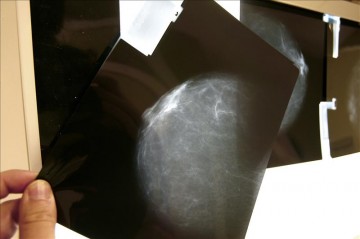

Bruselas, 27 oct (EFE).- Una investigación financiada por la Unión Europea (UE), cuyos resultados se darán a conocer en 2015, apuesta por tratamientos personalizados para los pacientes de cáncer de mama de forma que no siempre se recurra directamente a la quimioterapia.

Bruselas, 27 oct (EFE).- Una investigación financiada por la Unión Europea (UE), cuyos resultados se darán a conocer en 2015, apuesta por tratamientos personalizados para los pacientes de cáncer de mama de forma que no siempre se recurra directamente a la quimioterapia.

El proyecto MINDACT, gestionado por la Organización Europea para la Investigación y el Tratamiento del Cáncer (EORTC, en inglés), mantiene entre sus conclusiones previas que para entre un 10 y un 20 % de pacientes es más adecuado aplicar alternativas a la quimioterapia tras una intervención, informó la Comisión Europea (CE) en un comunicado.

Estas investigaciones señalan que la quimioterapia «aunque eficaz, puede traer consigo consecuencias como el desarrollo de cáncer secundarios, daño en el corazón, avance de la menopausia o reducción de algunas funciones cognitivas».

Asimismo, en algunos pacientes que aún están en una fase muy temprana, la quimioterapia puede resultar «un tratamiento por encima de lo necesario».

En el proyecto de investigación MINDACT han participado 6.600 mujeres de nueve países de la UE.

El de mama sigue siendo el segundo cáncer más común en el mundo y el más mortal para las mujeres, según los datos de la CE.

En la UE, hasta 364.449 mujeres fueron diagnosticadas de esa enfermedad en 2012.